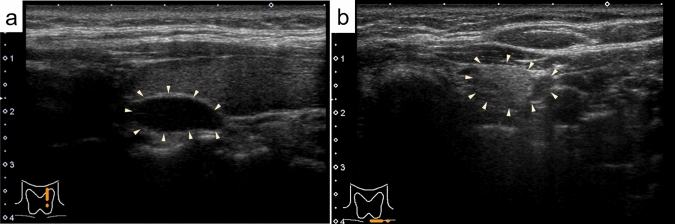

Results: Ultrasonography revealed a lipoadenoma detection rate of 20.0%. This increased to 80.0% at re-examinations performed after obtaining information from other imaging modalities. Compared with parathyroid adenoma cases with no adipocytes or few adipocytes, the frequencies of ill-defined margins, iso- and/or hyperechogenicity, heterogeneous consistency with a two-tone pattern, poor vascular flow, no polar artery, and no hyperechoic line were significantly higher in parathyroid lipoadenoma cases. The hyperechoic and isoechoic areas in tumors with a two-tone pattern correspond to adipocyte- and parathyroid cell-rich areas, respectively. The lipoadenoma tumor sizes measured using ultrasound tended to be smaller than the actual sizes.

Abstract Image